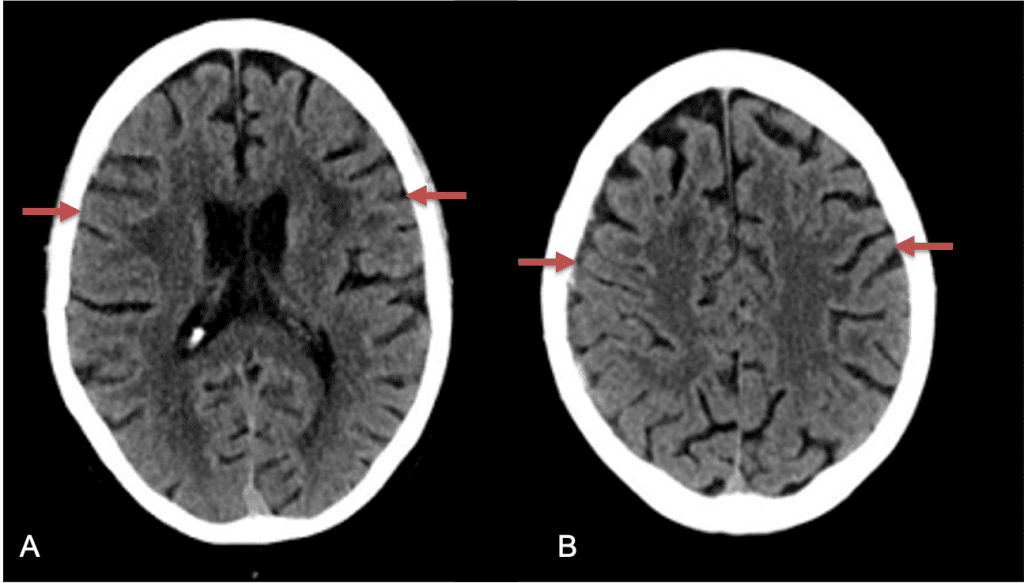

The patient agreed to receive minimally invasive treatment with Bilateral Middle Meningeal Artery Embolization, a new approach to promote resorption of chronic and subacute subdural hematomas in patients that are not improving with conservative measures or have contra-indications to surgical evacuation. Selective catheterization of the Middle Meningeal Artery is followed by transarterial embolization of the territory and inflammatory membranes that are felt to be secreting serosanguinous proteinaceous exceeding the capacity for resorption. MMA embolization was performed bilaterally in this patient. (Figure 2. A and B)

Figure 2. A) Initial right ECA angiogram ; B) Post MMA Embolization; C) Selective Embolization Of Middle Meningeal Artery Membranes using PVA particles (arrows).